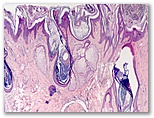

Lesión congénita en cuero cabelludo

Diagnostico